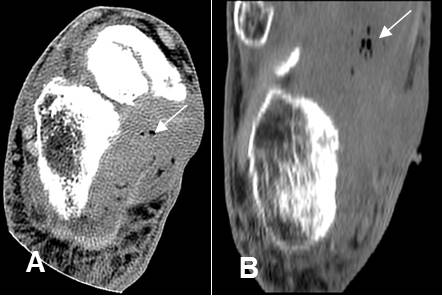

Fig 153. Miositis osificante.

A: Rx de cadera y B: TAC axial. 2 casos diferentes donde existe calcificación de tejidos blandos en relación con grupos musculares, por miositis osificante.